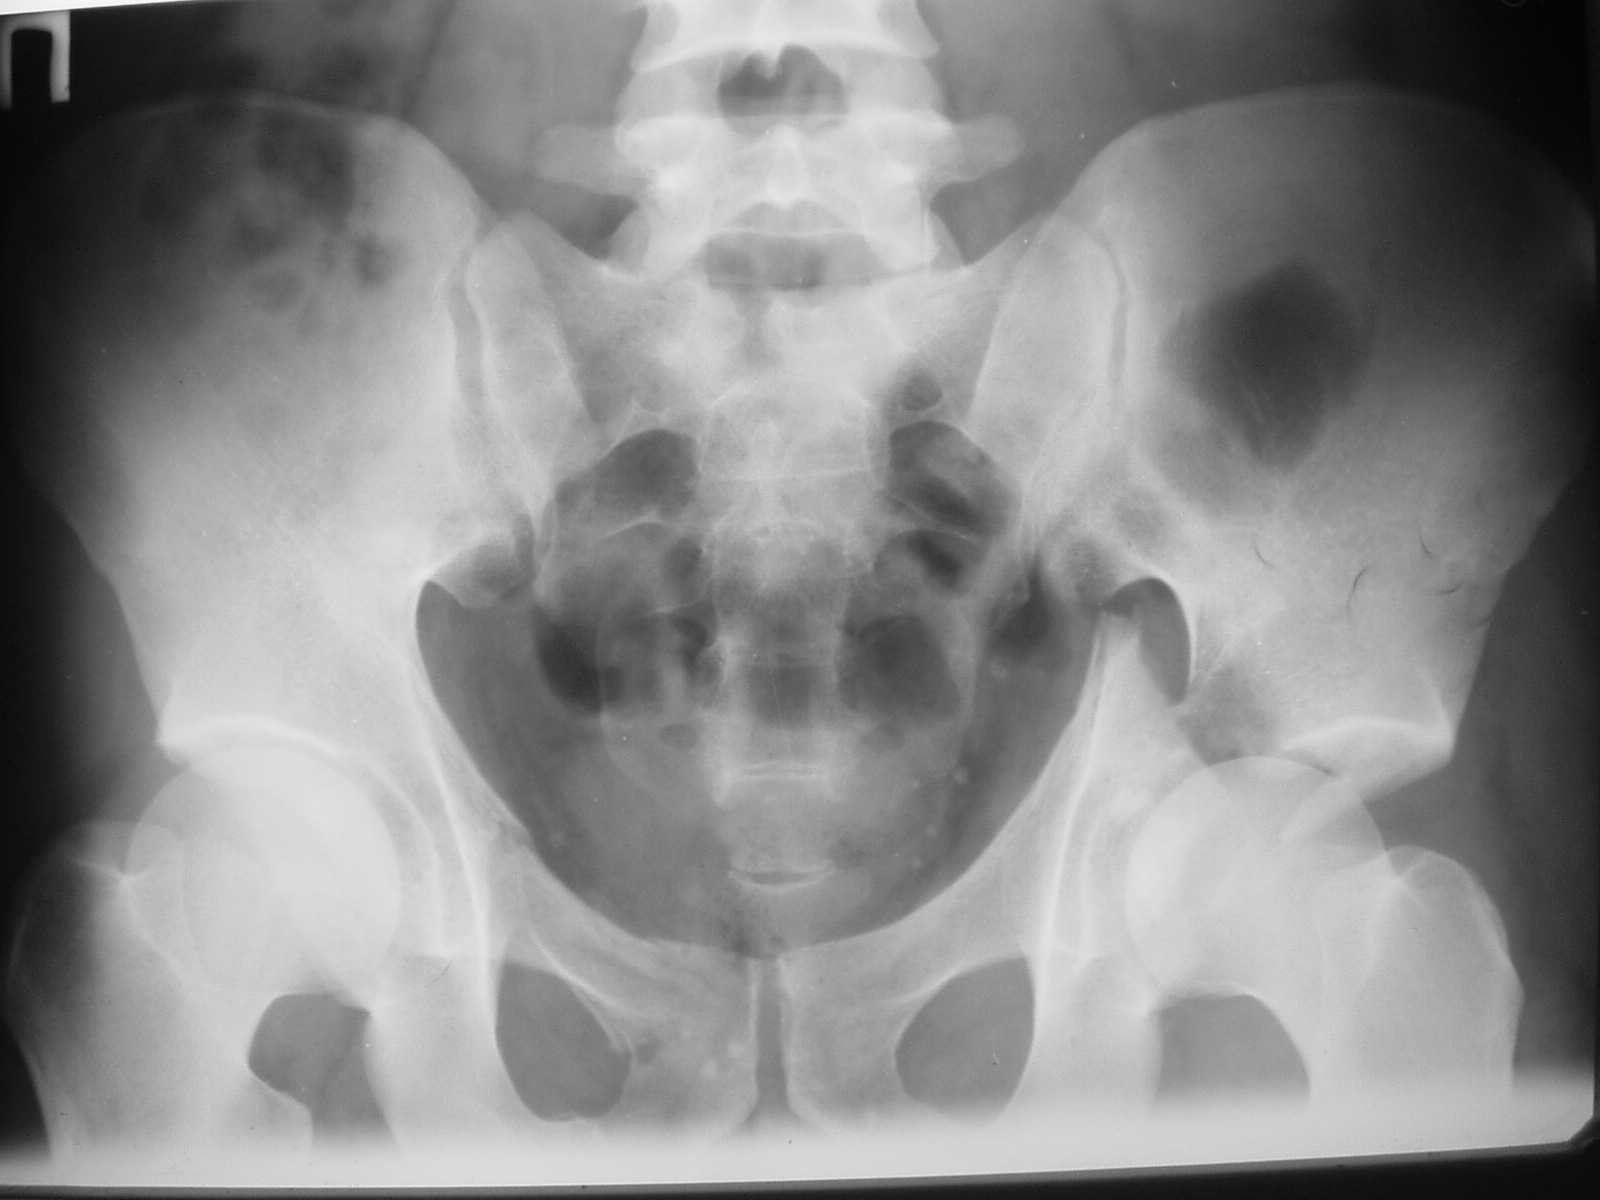

[Ortho] Acetabulum fracture

Dear dr Yordan !  I would do internal fixation as soon as possible. I sent to you one of my case with using of anterior iliofemoral approach - 5-th day after the accident. Best regards. Anatoliy Kanzyuba, MD. Donetsk Ukraine

Имя     : 2.JPG

Размер  : 60097 байтов